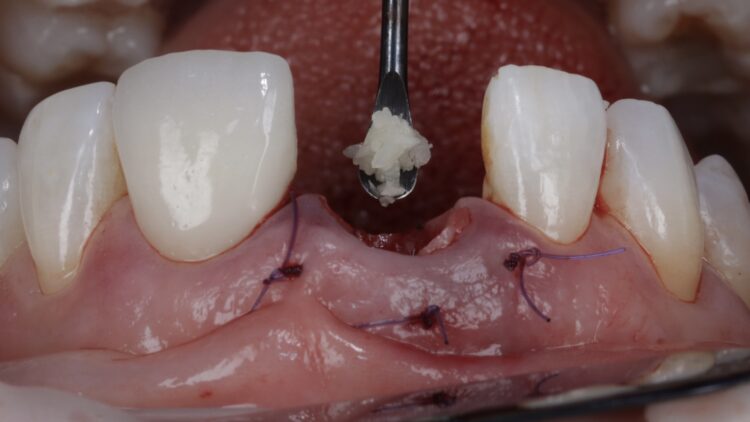

A free gingival graft was harvested from the palate, allowing enough tissue to reach between the base of each papilla and this was de-epithelialised to obtain the connective tissue. A thickness of 1mm is adequate, but in this instance, it was made intentionally thicker at the disto-buccal aspect to help plump up the papilla where bone loss was greater. The connective graft tissue was stabilised with three resorbable sutures placed, positioning the connective tissue graft 1mm below the free gingival margin.

A bone graft was then performed, adding MinerOss® Blend (BioHorizons Camlog) to the jump gap. This affords an ideal combination of cortical and cancellous bone, delivering high bone density and reliable revascularisation to ensure the fast and predictable turnover of bone.

The temporary restoration was then reintroduced and the surgical site closed tension-free. Vertical sling sutures were placed through both papillary areas over the contact points to hold the tissue up, create a prosthetic sealand to combat natural shrinkage.

A post-operative radiograph was taken to confirm that the crestal bone was not compressed and there was no convexity in the area to allow space for the soft tissue graft to expand, proliferate and grow.